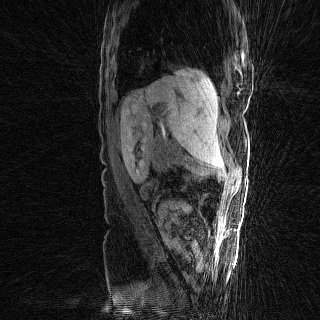

Deep neural networks for medical image reconstruction are traditionally trained using high-quality ground-truth images as training targets. Recent work onNoise2Noise (N2N) has shown the potential of using multiple noisy measurements of the same object as an alternative to having a ground truth. However, existing N2N-based methods cannot exploit information from various motion states, limiting their ability to learn on moving objects. This paper addresses this issue by proposing a novel motion-compensated deep image reconstruction (MoDIR) method that can use information from several unregistered and noisy measurements for training. MoDIR deals with object motion by including a deep registration module jointly trained with the deep reconstruction network without any ground-truth supervision. We validate MoDIR on both simulated and experimentally collected magnetic resonance imaging (MRI) data and show that it significantly improves imaging quality.